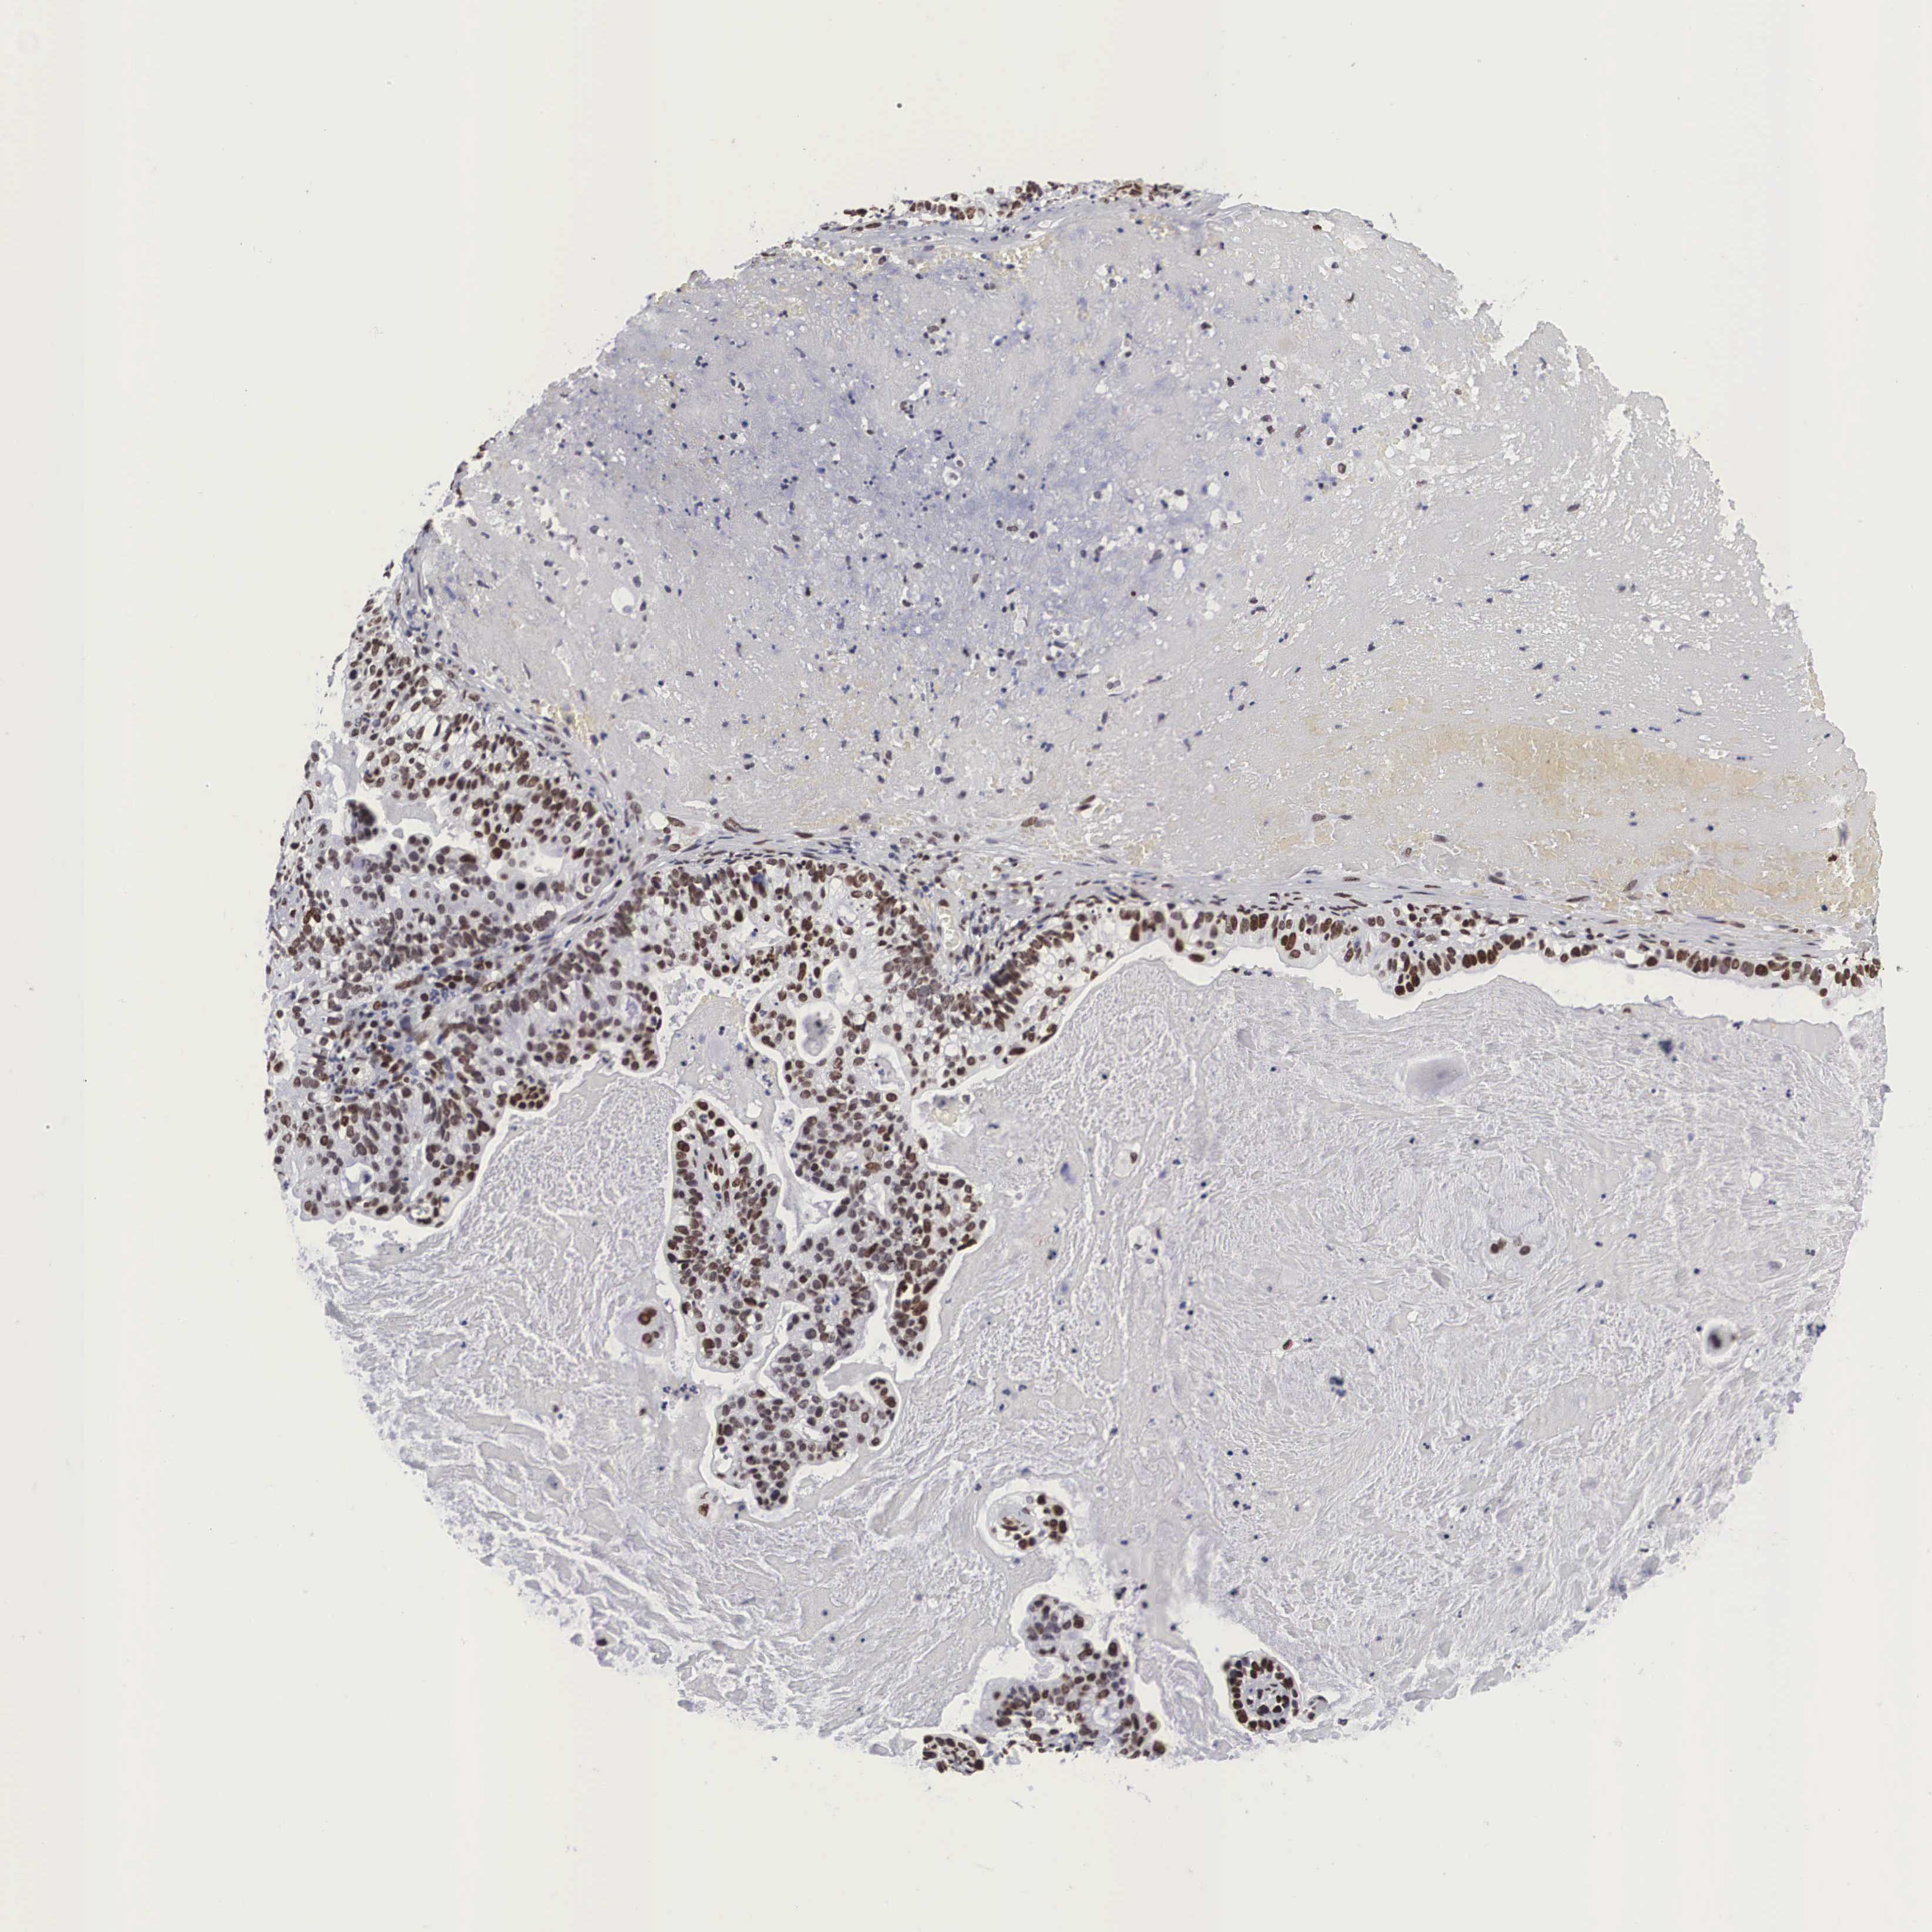

CERVICAL CANCER - Protein expressioni

A mouse-over function shows sample information and annotation data. Click on an image to view it in a full screen mode. Samples can be filtered based on level of antibody staining by selecting one or several of the following categories: high, medium, low and not detected. The assay and annotation is described here.

Note that samples used for immunohistochemistry by the Human Protein Atlas do not correspond to samples in the TCGA dataset.

Antibody stainingi

Antibody staining in the annotated cell types in the current human tissue is reported as not detected, low, medium, or high, based on conventional immunohistochemistry profiling in selected tissues. This score is based on the combination of the staining intensity and fraction of stained cells.

Each image is clickable and will lead to virtual microscopy that enables deeper exploration of all samples and also displays staining intensity scores, fraction scores and subcellular localization as well as patient and tissue information for each sample.

Antibody HPA000593

Antibody HPA001341

Antibody CAB037264

Staining

High

Medium

Low

Not detected

Intensity

Strong

Moderate

Weak

Negative

Quantity

>75%

75%-25%

<25%

None

Location

Nuclear

Cytoplasmic/membranous

Cytoplasmic/membranous,nuclear

Adenocarcinoma, NOS

Squamous cell carcinoma, NOS